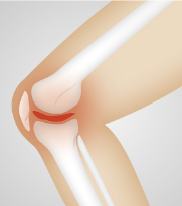

무릎 인공관절이란 무릎 관절의 연골이나 뼈가 심하게 손상되어 통증이나 기능장애가 있는 환자들에게 수술적으로 삽입하는 인공적인 관절입니다. 무릎 인공관절은 금속과 플라스틱으로 만들어져 있으며, 마모된 무릎 관절의 일부나 전체를 대체합니다.

무릎 인공관절이 필요한 경우는 주로 **퇴행성 관절염** 때문입니다. 퇴행성 관절염은 연령이나 과도한 운동, 외상, 비만 등의 원인으로 인해 연골이 점차 닳아가는 질환입니다. 연골은 뼈와 뼈 사이에 있는 부드러운 조직으로, 뼈의 마찰을 줄여주고 충격을 흡수하는 역할을 합니다. 연골이 닳으면 뼈와 뼈가 직접 부딪치게 되어 통증이나 염증, 관절의 변형이 발생합니다.